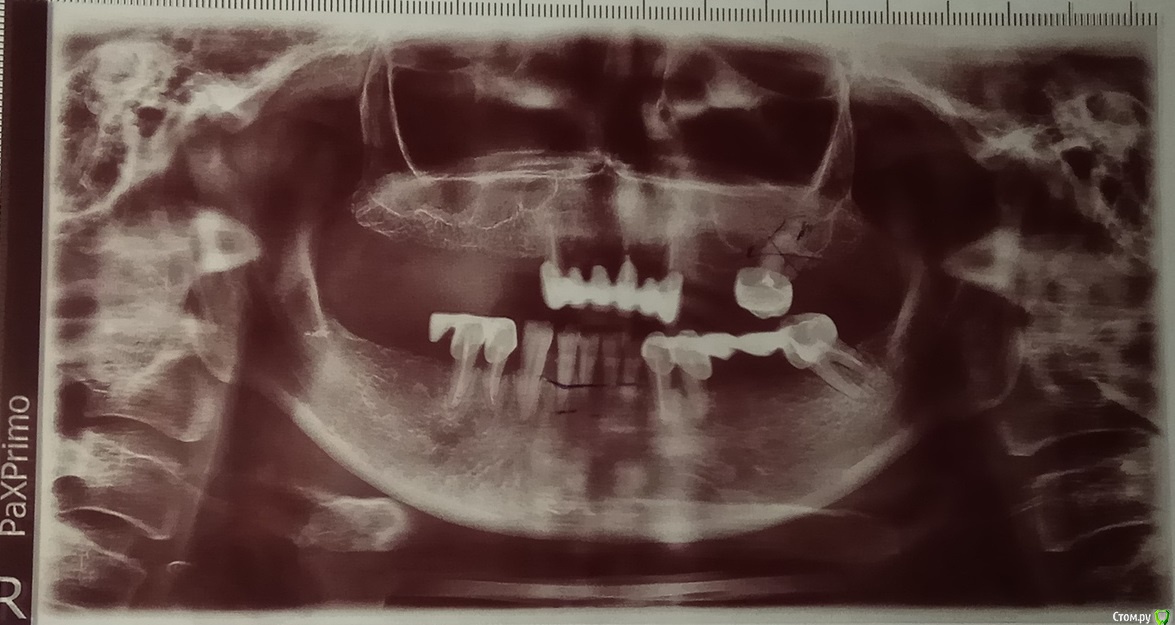

chervoncevdaniil Опубликовано 9 февраля, 2019 Поделиться Опубликовано 9 февраля, 2019 В вашем случае принципиально вариантов два:полное съемное протезирование,либо различные варианты протезирования на имплантах,но они оба подразумевают удаление зубов.К сожалению,прогноз зубов,которые у вас остались в долгосрочной перспективе неблагоприятный.Вариант полного съемного протезиования на нижней челюсти без опоры на зубы и импланты рекомендую максимально избегать 2 Ссылка на комментарий

chervoncevdaniil Опубликовано 10 февраля, 2019 Поделиться Опубликовано 10 февраля, 2019 (изменено) Спасибо за ответ.В таком случае хотелось бы узнать, можно ли отказаться от полного удаления зубов на нижней челюсти и осуществить неполное съемное протезирование, и какие, в таком случае, зубы точно подлежат удалению и какой способ протезирования было бы лучше использовать?Если вы какие то зубы оставите на нижней челюсти,то протез годика через 3 их раскачает окончательно и все равно вам придется их удалять и заново перепротезироваться по новой,т.е. оставляя зубы вы должны быть к этому готовы.Лучшим вариантом будет протезирование на нижней челюсти с опорой на импланты,а уж выбор конструкции и количества имплантов будет зависеть от вашего бюджета,потому что на имплантах можно делать разные конструкции,вплоть до несъемных.но это будет по итогу все равно дешевле,чем сейчас заплатить за сохранение зубов и изготовление протеза,который через пару лет все равно придется переделывать Изменено 10 февраля, 2019 пользователем chervoncevdaniil 1 Ссылка на комментарий